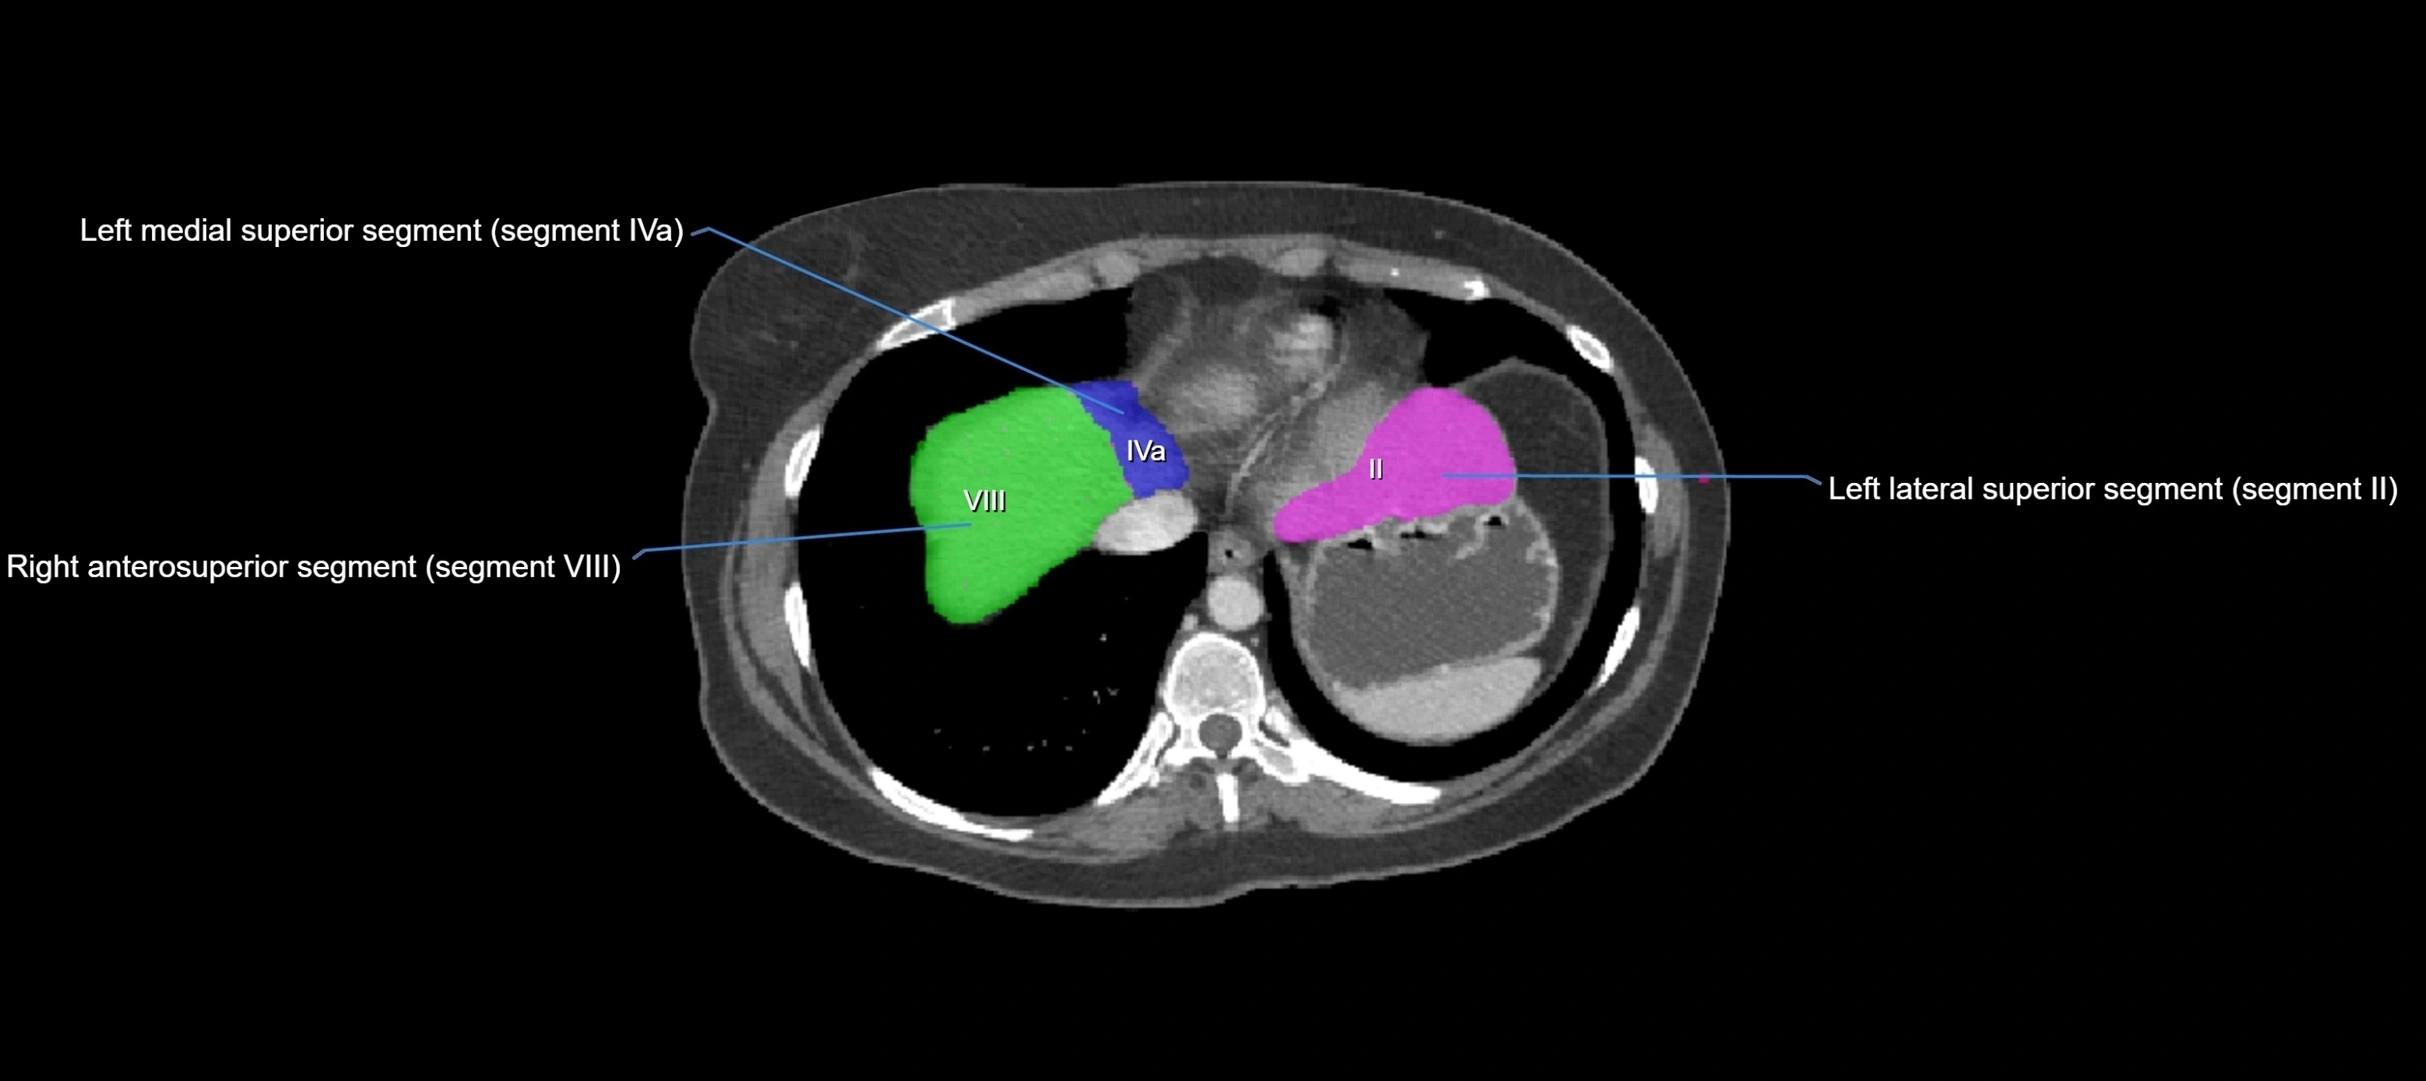

MRI image

image